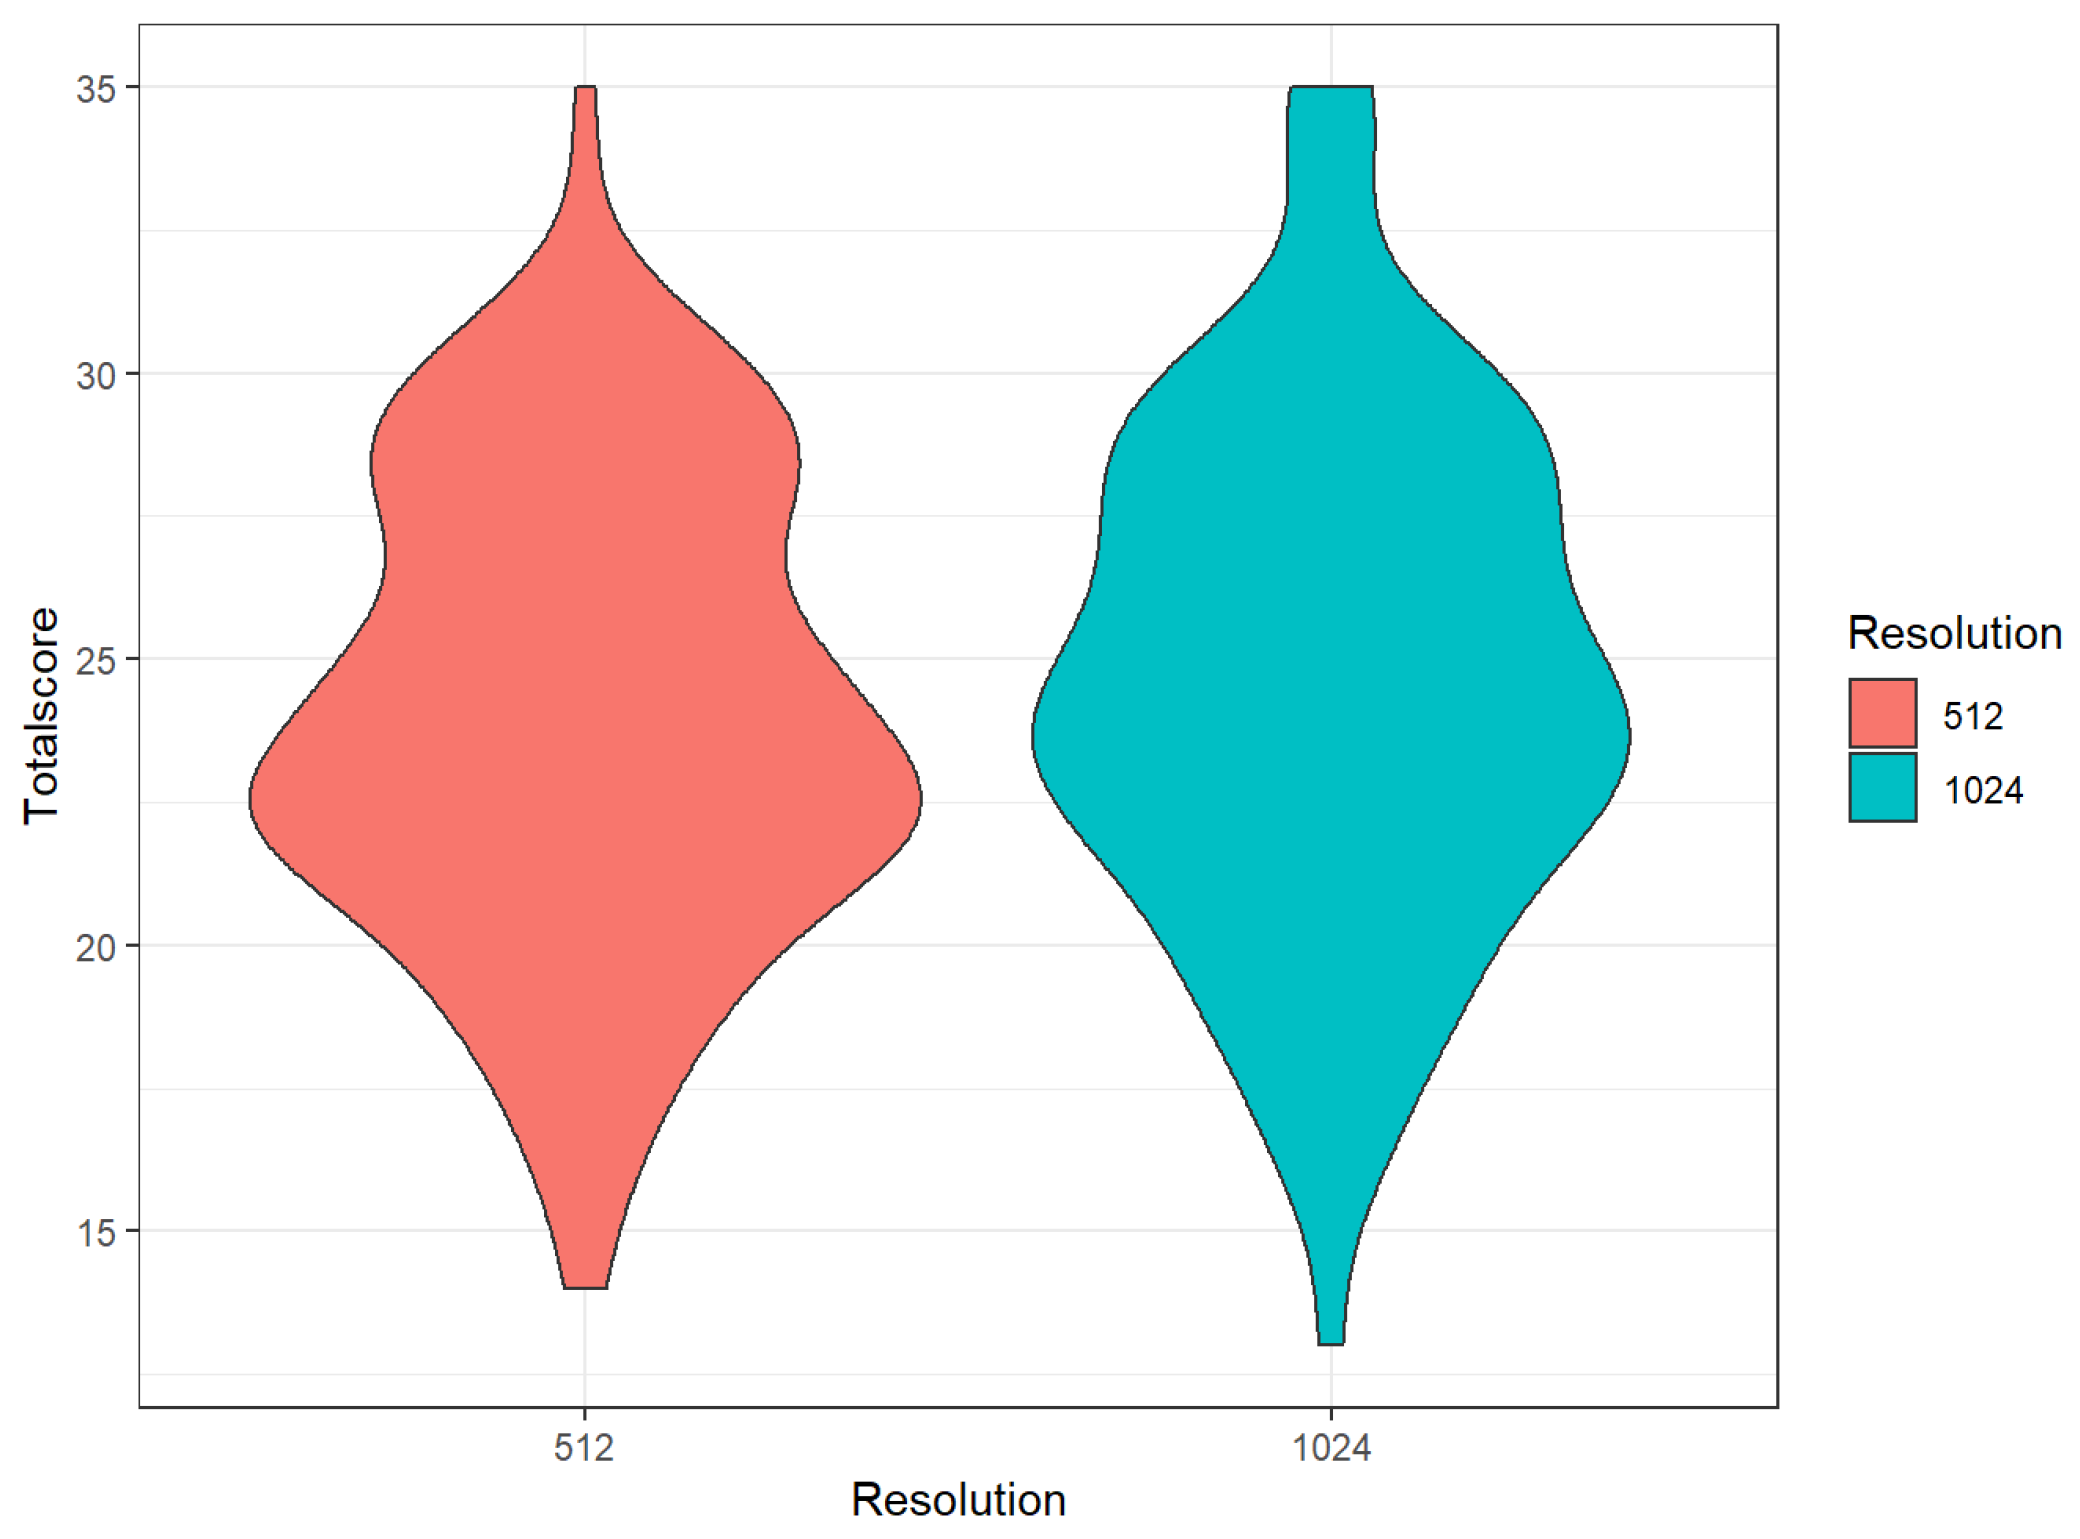

3.3. Comparison of Different Matrices

| 512 | 1024 | p (Wilcox.) | |||

|---|---|---|---|---|---|

| Mean | Sd | Mean | Sd | ||

| Sharpness | 3.64 | 0.98 | 4.18 | 0.76 | <0.01 |

| Noise | 3.81 | 0.70 | 3.72 | 0.86 | 0.09 |

| Depiction of bronchiole | 3.53 | 0.74 | 3.72 | 0.83 | <0.01 |

| Overall image impression | 3.70 | 0.76 | 3.89 | 0.77 | <0.01 |

| Extent RBF | 2.99 | 1.38 | 2.94 | 1.40 | 0.49 |

| Extent GGO | 3.05 | 1.27 | 2.91 | 1.31 | 0.04 |

| Total | 24.08 | 4.09 | 24.71 | 4.46 | <0.01 |